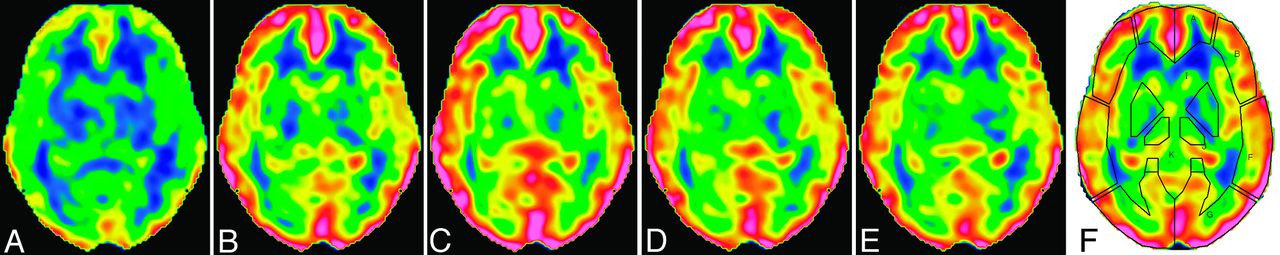

CBF images with acceptable qualities were obtained serially after ACZ injection, and augmentation of CBF was noted visually (Fig 1). ROIs were successfully placed by use of the 3D-SRT software, providing an absolute rCBF value for each brain region. The mean rest rCBF calculated from the first scan was 51.9 ± 4.5, 52.4 ± 5.0, 51.6 ± 5.3, and 50.1 ± 8.0 mL/min per 100 g in the anterior cerebral artery, ant-MCA, post-MCA, and posterior cerebral artery regions, respectively. The rCBF started to increase just after ACZ injection, peaked at approximately 10 minutes, and then decreased slowly (Fig 2). The temporal patterns of cerebrovascular response were similar among the brain regions.

CBF images at the level of the basal ganglia in a 28-year-old woman. Data were acquired with a NEX of 2 and a postlabeling delay of 1525 ms at rest (A) and 3 minutes (B), 9 minutes (C), 15 minutes (D), and 31 minutes (E) after acetazolamide injection. The time indicates the mid time of data acquisition. The upper and lower limits of the color scale are set at 110 and 0 mL/min per 100 g, respectively. F, ROIs placed automatically by the 3D-SRT software.